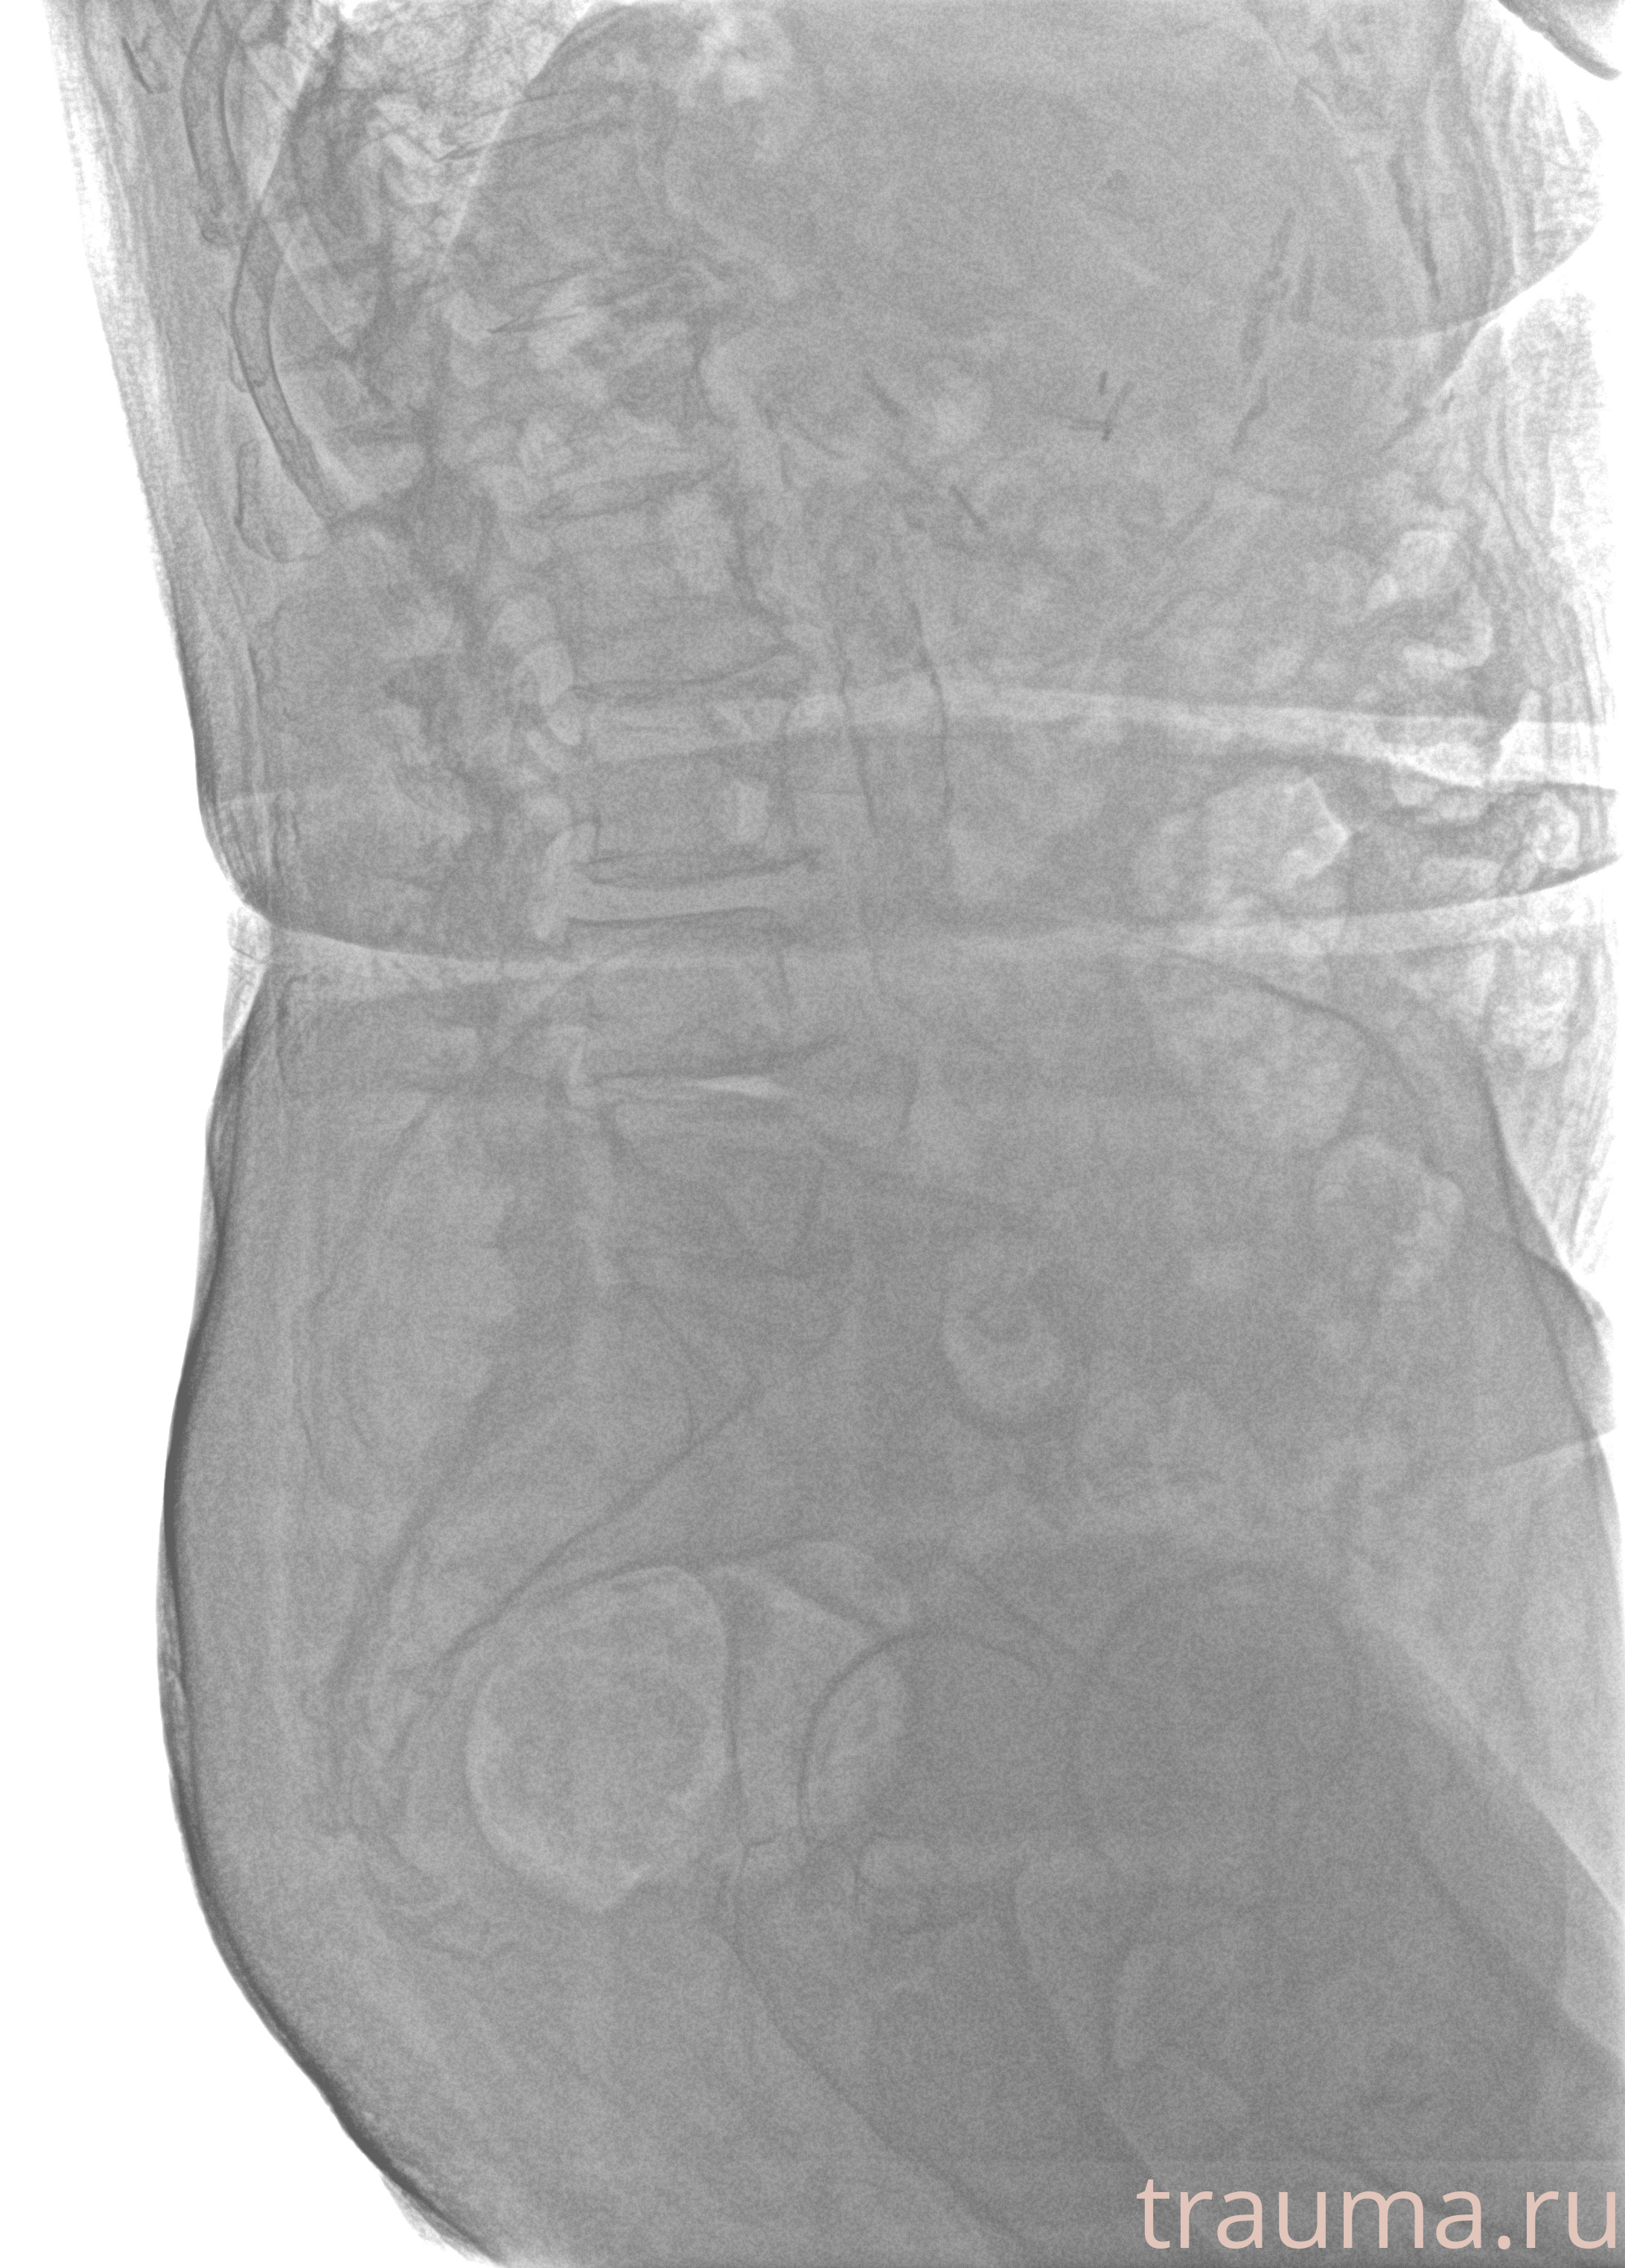

Рентгенограммы

Рентген на дому: по вашему адресу приезжает врач-рентгенолог, травматолог-ортопед с мобильным рентгеновским аппаратом, проводит диагностику травмы или заболевания, делает необходимые рентгенограммы, дает рекомендации по дальнейшему лечению. Получить качественные снимки в домашних условиях возможно благодаря уникальной методике, разработанной МосРентген Центром для института  Склифосовского

при переломе шейки бедра и пневмонии от компании МосРентген Центр - партнера Института имени Склифосовского